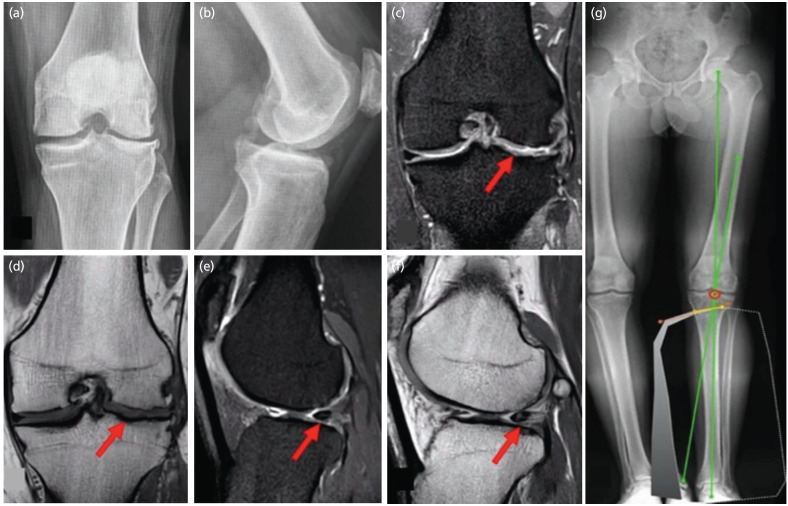

不同的手术技术用于保护膝关节软骨退化;然而,结合这些技术可能具有挑战性。本病例描述了一名35岁男性,双膝内翻错位并伴有左膝疼痛,诊断为股骨外侧4级软骨病变,复杂外侧半月板病变,内侧半月板径向撕裂。患者采用胫骨近端三维模型行外翻胫骨截骨术、外侧骨软骨异体移植和外侧半月板异体移植。术后17个月,他经历了扭转创伤,导致移植的半月板后根撕裂和前交叉韧带损伤。随后的手术探查显示了软骨保护改变的证据,包括同种异体股骨骨软骨移植愈合和移植半月板的生物力学整合,如半月板外侧根撕裂发展所示。本病例强调了结合这些外科手术实现移植半月板生物力学整合的潜力,有助于累积软骨保护作用。

Different surgical techniques are used to preserve knee articular cartilage deterioration; however, combining these techniques can be challenging. This case study describes a 35-year-old man with bilateral genu varum malalignment and left knee pain, diagnosed with a grade IV chondral lesion in the lateral femur, a complex lateral meniscus lesion, and a radial tear in the medial meniscus. The patient underwent a valgus-producing tibial osteotomy, lateral osteochondral allograft transplantation, and lateral meniscal allograft transplantation using a 3D model of the proximal tibia. Seventeen months post-operatively, he experienced torsional trauma, leading to a tear of the transplanted meniscus posterior root and an anterior cruciate ligament injury. Subsequent surgical exploration revealed evidence of chondroprotective changes, including femoral osteochondral allograft healing and biomechanical integration of the transplanted meniscus, as indicated by the lateral meniscus root tear development. This case highlights the potential of combining these surgical procedures to achieve biomechanical integration of the transplanted meniscus, contributing to cumulative chondroprotective effects.